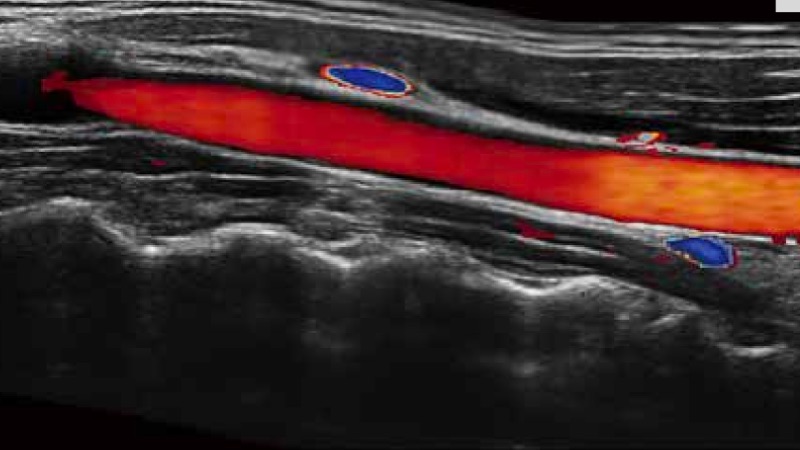

实时宽景成像技术

通过彩色血流和实时宽景相结合,可观察到完整的动静脉血流,方便医生检查。实时扫查过程中,如有任何操作失误也可以很容易地进行回扫擦除,而不会中断扫查。